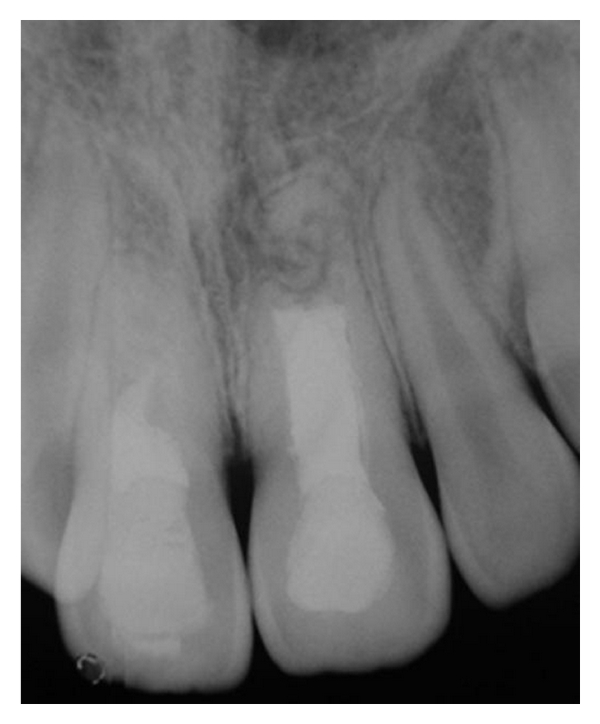

On January 2007, an 8-year-old boy suffered an injury in a playground see-saw affecting the region of maxillary anterior teeth. His parents sought for professional care in a pediatric dentistry clinic 5 days after the accident. At this occasion, a severe intrusive luxation of tooth 11 was diagnosed (more than 6 mm of intrusion from the incisal line (according to the classification of the Royal College of Surgeons of England [5]). In addition, root fractures of the apical third of both maxillary central incisors were also noticed in the radiograph (Figure 1). The patient was referred to both specialized endodontic and orthodontic care.